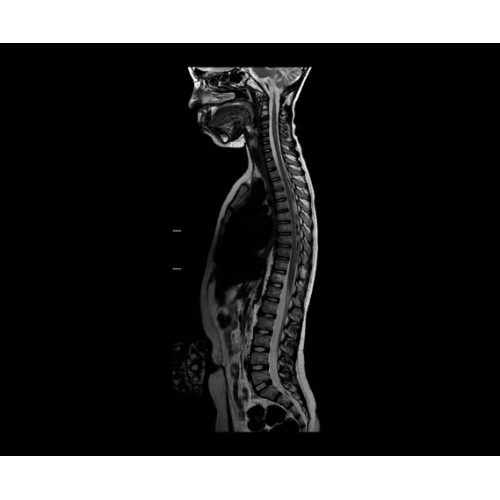

• NeuroWorks — универсальное решение для визуализации анатомии головного мозга, позвоночника, сосудов и периферических нервов с четкой дифференциацией тканей.